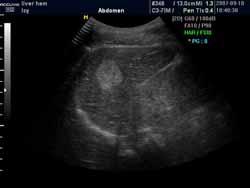

超聲引導(dǎo)下的局部治療也就是在彩超的實時引導(dǎo)下,通過經(jīng)皮肝穿刺將硬化劑、抗血管生成的藥物直接注入瘤體內(nèi)部,能使血管瘤組織脫水固定,組織細胞蛋白質(zhì)凝固變性,局部血管血竇內(nèi)皮壞死,血栓形成,導(dǎo)致細胞死亡和纖維化,從而達到治療目的。治療方法簡單,不需要特殊設(shè)備,痛苦小,療效明確。

(血管瘤超聲表現(xiàn)可見高回聲血管團影)

(超聲穿刺針直接對瘤體進行注射治療)